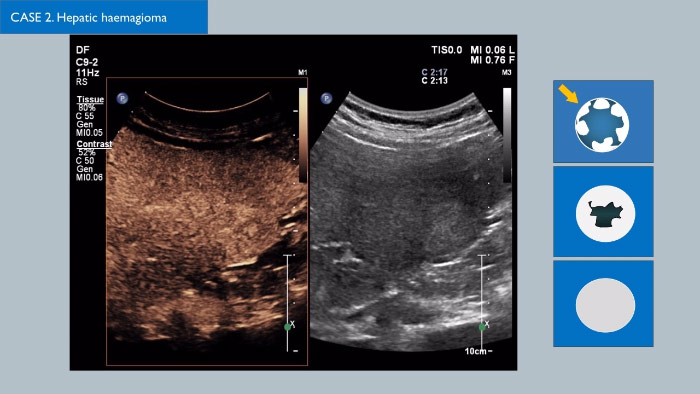

Os agentes de contraste de ultrassom conseguem transformar a função do ultrassom, permitindo aos médicos estudar os padrões de melhoria de lesões hepáticas em tempo real, proporcionando diagnósticos mais rápidos e definitivos.

Com o ultrassom da Philips, a ultrassom com realce por contraste está perfeitamente integrada no fluxo de trabalho padrão, fornecendo detalhes excecionais durante os exames de fase arterial, portal e tardia. Além disso, com tecnologias avançadas como o MaxVue, o transdutor PureWave C9-2, a imagiologia de fusão e a quantificação integrada através das Q-Apps da Philips e ainda a melhor solução no âmbito hepático, é possível obter a confiança máxima mesmo nos exames tecnicamente mais difíceis. Soluções inovadoras como a tecnologia 3D/4D xMatrix também podem transformar a avaliação de lesões hepáticas, fornecendo uma forma rápida e eficaz de visualizar vasos de alimentação e a resposta aos tratamentos. Existem muitos desenvolvimentos interessantes no campo da CEUS; clique na ligação para entrar em contacto com o seu representante de vendas local da Philips.